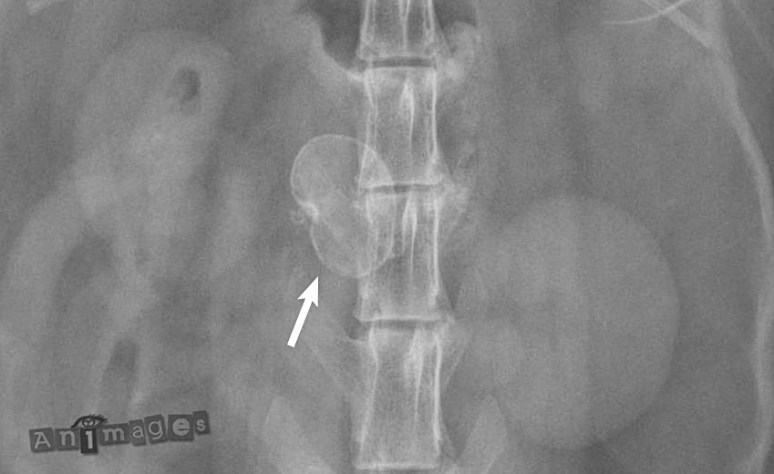

Un 3e rein minéralisé ? Pas tout à fait…

Cette opacité minérale n’avais rien à avoir avec les néphrons, mais avec les adipocytes qui, sans raison apparente, se mettent à nécroser, puis à calcifier. Ce processus laisse une petite masse – ou parfois plusieurs – dans la cavité abdominale de certains chiens et chats, plutôt vieux et obèses. La forme de coquille au contour lisse – ou parfois lobulé – est typique sur les radiographies. À ne pas confondre avec une tumeur ou granulome qui se calcifient généralement de façon plus hétérogène – lorsqu’il le font – ou avec un corps étranger. La localisation extra-digestive était peut-être évidente dans ce cas-ci, mais attention, ce n’est pas toujours le cas ! Cette nécrose adipeuse peut impliquer le ligament falciforme, le mésentère, l’omentum ou autre structure graisseuse dans l’abdomen. Évidemment, si c’était un lapin, on aurait tout de suite penser à un oeuf, mais bon 😉